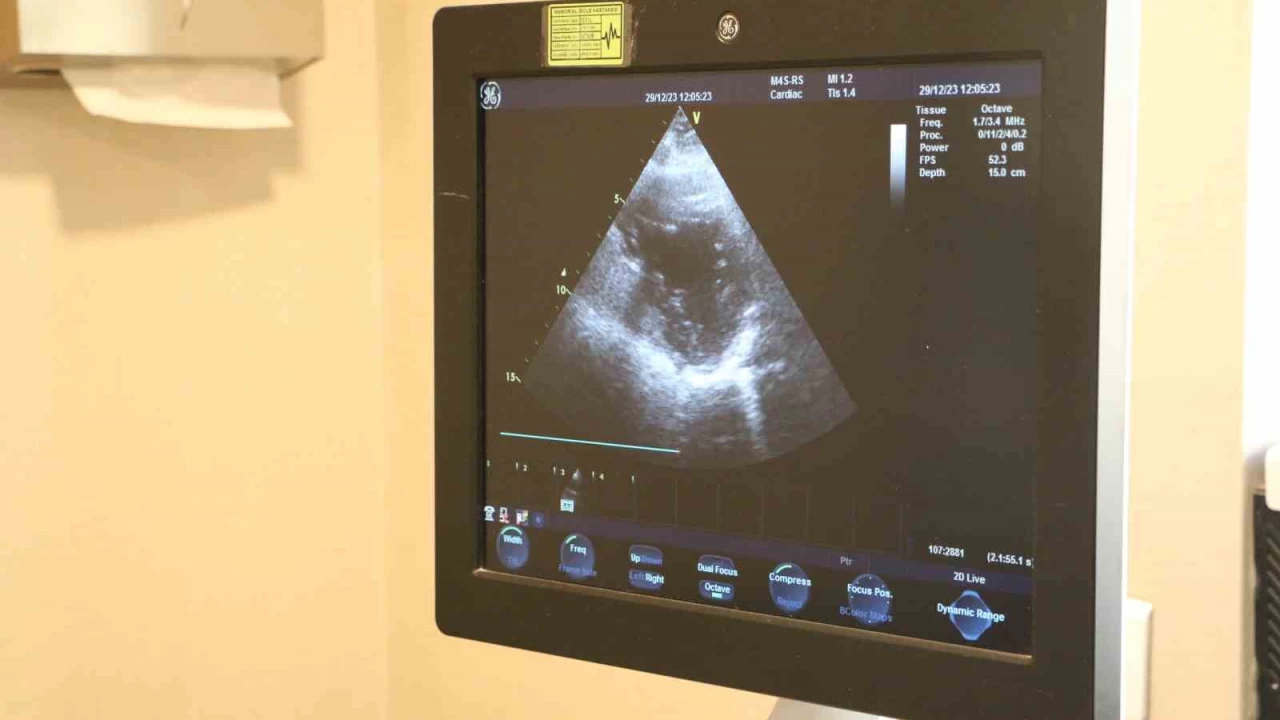

Ayaktaki şişkinlik kalp kapak hastalığı habercisi olabiliyor

Kalp rahatsızlıklarında erken tanının önemli olduğunu söyleyen Kardiyoloji Uzmanı Doktor Hüseyin Akçalı, 'Kalp kapak hastalıklarının belirtileri; halsizlik, çabuk yorulma, nefes darlığı, ayaklarda şişkinlik olarak nitelendirebiliriz temel olarak, baş dönmesi, baygınlık. Bunlar kalp kapak hastalığının belirtileri olabilir' dedi.

Uzman doktor, kalp kapak hastalıklarının son yıllarda özellikle ileri yaştaki kişilerin sıklıkla karşılaştığını belirtiyor. Kişilerin yaşam standartlarını etkileyen bu hastalık, düzenli tedavisinin yapılmadığı takdirde ölümle sonuçlanabiliyor.

Uzman Doktor Hüseyin Akçalı, geçirilmiş kalp krizi sonrası özellikle kalp kapak hastalığını ortaya çıkabileceğini söyledi.

Kalp kapaklarının vücutta 4 tane bulunan, kan akışını sağlayan ve kan akışına yön veren kapaklar olduğu bilgisini veren Dr. Akçalı, "Kalp kapak hastalıkları, zamanla yaşa bağlı olarak ortaya çıkabileceği gibi geçirilmiş enfeksiyona bağlı konjenital olarak ya da travmaya bağlı ortaya çıkabilir. Geçirilmiş kalp krizi sonrası da kalp kapak hastalığı ortaya çıkabilir. Kalp kapak hastalıklarının belirtileri; halsizlik, çabuk yorulma, nefes darlığı, ayaklarda şişkinlik olarak nitelendirebiliriz temel olarak, baş dönmesi, baygınlık. Bunlar kalp kapak hastalığının belirtileri olabilir' dedi.

Kalp kapak hastalarının düzenli takibinin yapılması gerektiğine dikkat çeken Akçalı, 'Kalp kapak hastalarının düzenli takip yapmaları kesinlikle şart. Hastalık çeşidine göre, derecesine göre aylık veya yıllık periyodik olarak takip öneriyoruz. Özellikle ileri yaşta daha çok kalp kapak hastalığı görmekle birlikte çocuk yaşlarda ve erişkin yaşlarda da görebilmekteyiz. Genetik faktörler nadir de olsa kalp kapak hastalıklarını etkileyebiliyor' ifadelerinde bulundu.

Kalp kapak hastalıklarının hayati risk oluşturabileceğini vurgu yapan Akçalı, şunları kaydetti:

'Özellikle son dönemde ilerlemiş kalp kapak hastalıkları, ölüm dahi her türlü riski içerebiliyor. Düzenli takip ve tedaviyi bunun için öneriyoruz. Hastalığı olan bireylerin özellikle önce takiplerini aksatmamaları gerekiyor. Kardiyoloji polikliniğinde hekimin belirlediği aralıklı düzenli bir şekilde takibinin yapılması gerekiyor. Gerektiği noktada da cerrahi işlem yapılması gerekiyor. Kalp kapak hastalığı olan vatandaşların ileri efor sarf eden spordan uzak durması gerekiyor.'İHA